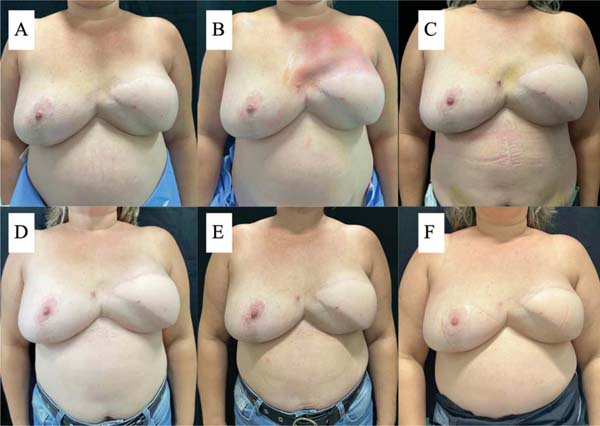

Standardized photographs were taken whenever patients underwent an ultrasound for visual monitoring. Images were obtained against a black background in anteroposterior, oblique (right and left), and lateral (right and left) views at a distance of 1.5 m using an iPhone 15 Pro (Apple, Inc.) camera.

In the decanted graft group, the average reduction compared with the initial thickness after lipofilling was 9.90% on day 15, 19.27% on month 1, 23.59% on month 3, and 26.36% on month 6. In the filtered graft group, the average reduction compared to the initial thickness after lipofilling was 7.74% on day 15, 14.85% on month 1, 20.67% on month 3, and 22.80% on month 6 (►Fig. 6). ►Figs 7–8 reveal the ultrasound change in subcutaneous tissue’s thickness before and after lipofilling. ►Figs. 9–10 show the pre-and postoperative results of one patient from each group.